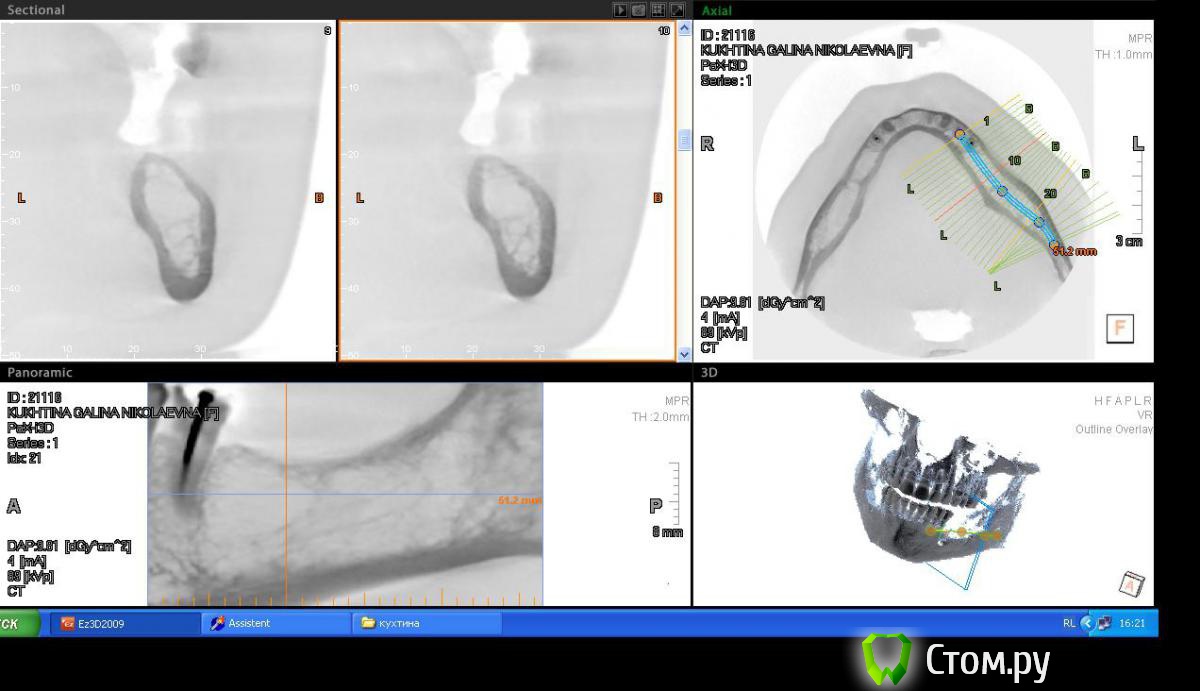

Пишем пациенту (45 лет, женщина) план ортопедического лечения, возможно с имплантами, возможно нет, пока думаем.

привлек внимание беззубый участок 36,37 зубов, уж очень большая лакуна получается, как вы думаете, онкология возможна или просто структура кости такая.

Если структура такова (склоняюсь к этому варианту, основываясь на отсутствии клиники, по контрастности на снимке, не отягощенн. анамнез), то как считаете, первичной стабильности имплантата добьемся за счет кортикалки? Или лучше в подобню яму не лезть и придумать бюгель, с другой стороны нет только 5,6,7.

Во рту клиники никакой нет.На орто ничего не видно. Жалоб нет.

прикрепил снимки в инверсии, лучше видно))